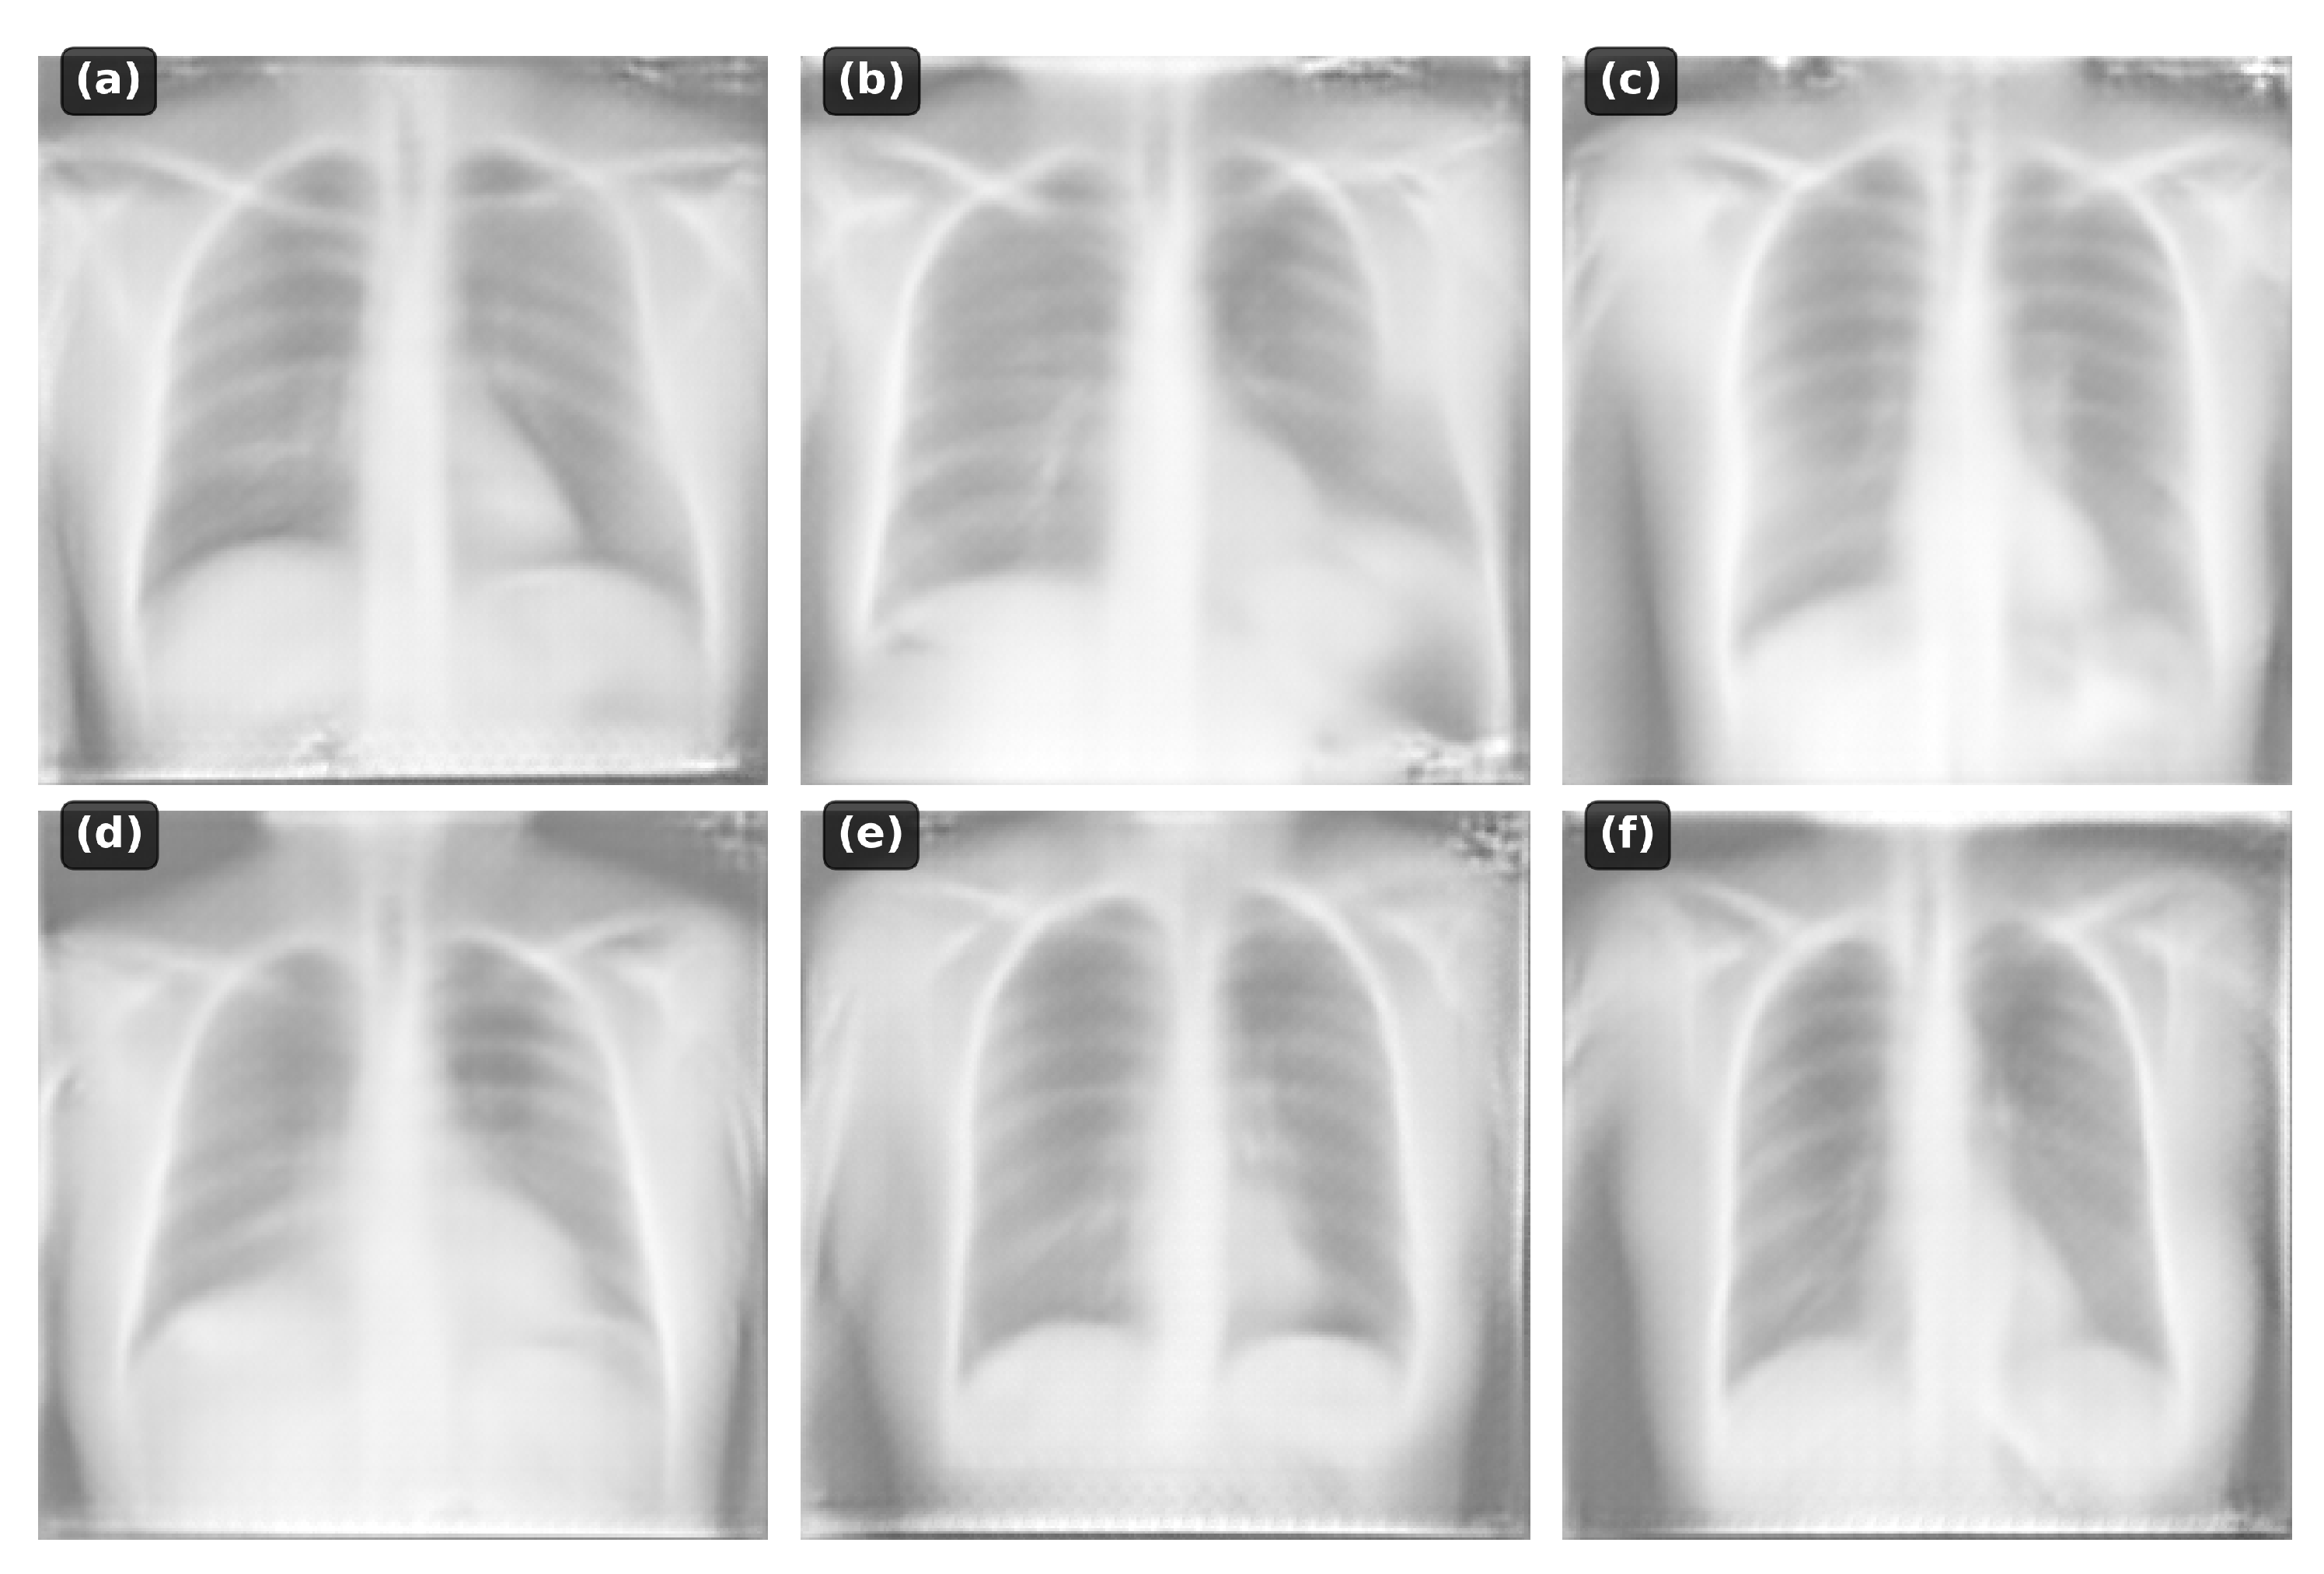

4.5. Qualitative Analysis

- Normal anatomy: Clear lung fields, normal cardiac silhouette

- Pneumonia: Focal consolidations in appropriate locations

- Cardiomegaly: Enlarged cardiac silhouette

- Pleural effusion: Blunting of costophrenic angles

- Pneumothorax: Absence of lung markings